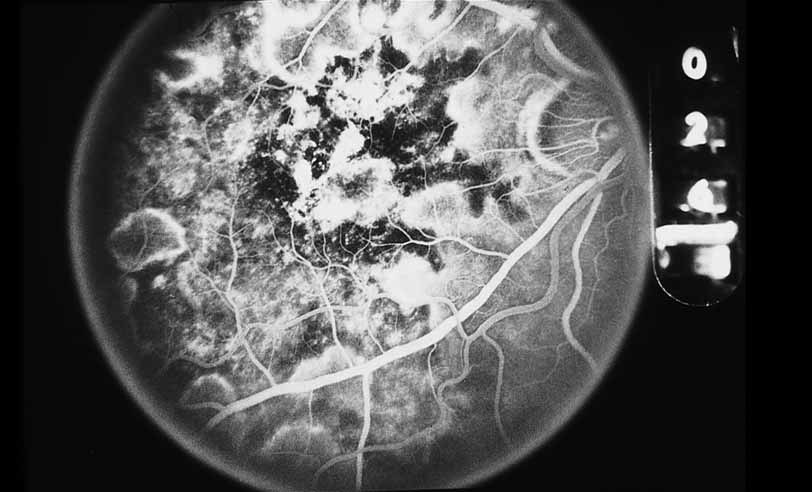

A variety of inflammations and infections, most notably presumed ocular histoplasmosis syndrome (see Figs. 37 and 38), serpiginous choroiditis, and multifocal choroiditis (see Figs. 39, 40, 41, and 42),1,89,90 are associated with the late complication of choroidal neovascularization. Probably the single most important application of fluorescein angiography in infectious and inflammatory diseases of the posterior segment is for the evaluation and potential treatment of this complication. In some instances, fluorescein angiography may be the single best method to determine whether visual loss seen late in the course of such disease as paramacular toxoplasmosis or serpiginous choroiditis is the result of secondary choroidal neovascularization or inflammatory disease recrudescence. In other diseases, such as presumed ocular histoplasmosis syndrome or multifocal choroiditis, choroidal neovascularization may occur early and be suspected on the basis of associated hemorrhage or lipid exudation. In some instances, even with the benefit of high-quality fluorescein angiography it may be difficult to distinguish between choroidal vasculitis and choroidal neovascularization superimposed on underlying choroiditis. We have recently identified a subgroup of young female patients, frequently darkly pigmented, who develop solitary zones of elevated choroiditis that have features of choroidal neovascularization. These appear to have a more indolent course than either idiopathic choroidal neovascularization or that associated with atypical multifocal choroiditis.

Fig. 39 Multifocal choroiditis. Color photograph of the macula shows multiple lesions and an area suspicious for choroidal neovascularization.

Fig. 40 Multifocal choroiditis. Fluorescein angiography confirms the presence of a subfoveal choroidal neovascular membrane.

Fig. 41 Multifocal choroiditis. Color photograph shows multiple small choroidal lesions scattered throughout the posterior pole.

Fig. 42 Multifocal choroiditis. ICG angiography shows multiple hypofluorescent spots in the distribution of the choroidal lesions seen on color photography.